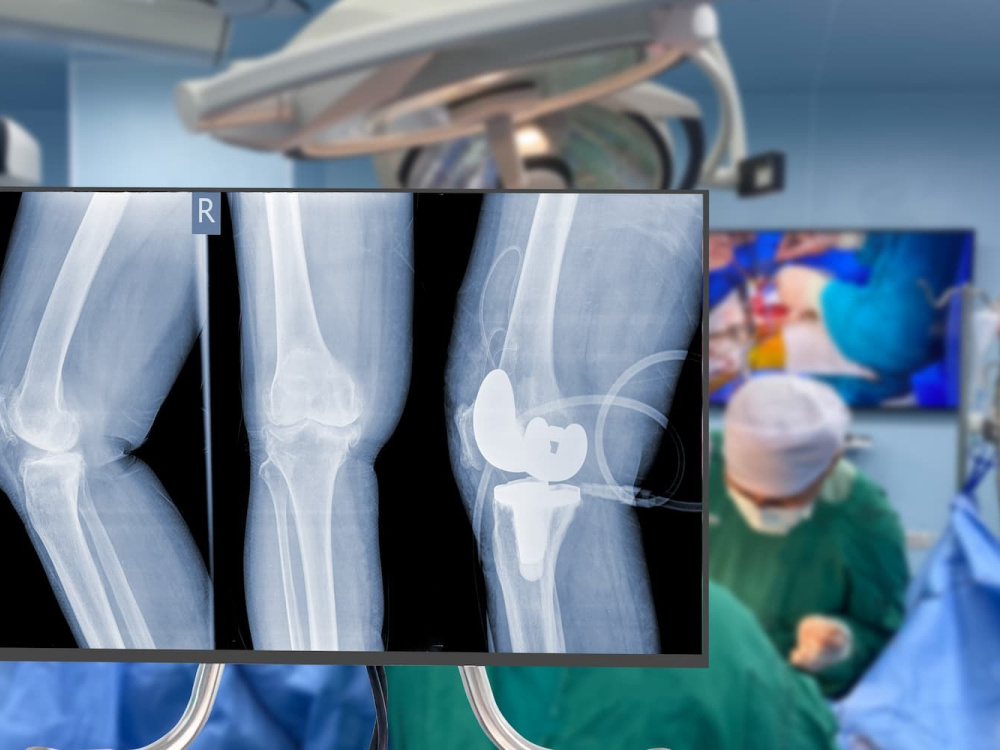

Les ménisques, ces coussinets cartilagineux en forme de C situés dans le genou, agissent comme un amortisseur et jouent un rôle crucial dans la flexibilité et l'absorption des chocs de l'articulation. Malheureusement, une lésion du ménisque peut provoquer des douleurs, des blocages et une réduction de la mobilité, affectant considérablement votre bien-être quotidien.

Heureusement, la méniscectomie ou chirurgie du ménisque, est une procédure courante et extrêmement efficace pour restaurer la fonction du genou. Nos cliniques collaboratrices en Turquie adoptent des méthodes avancées pour offrir des soins de qualité supérieure à des prix abordables.